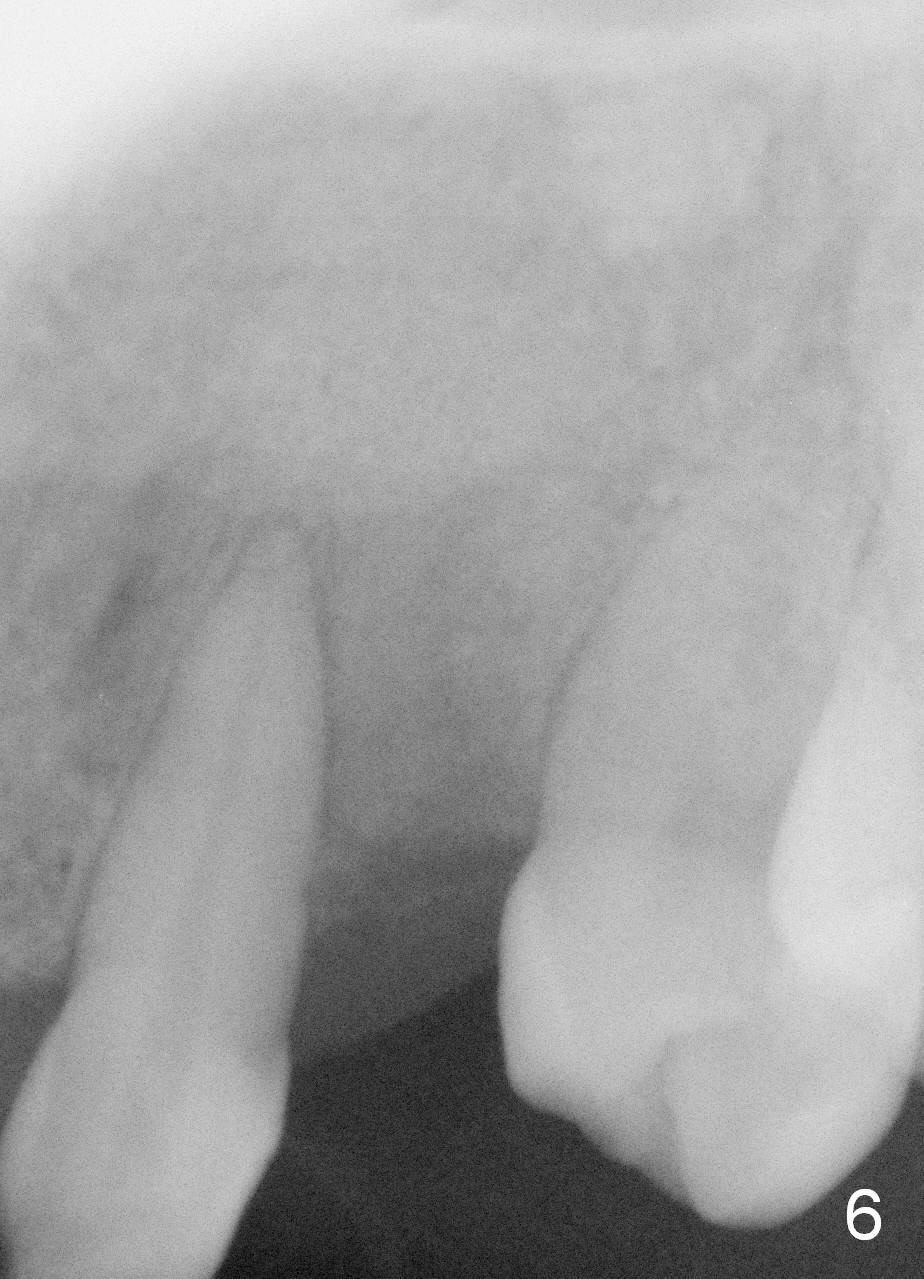

One month post-implantation at the site of the upper left deciduous canine, the patient returns for follow-up with chief complaint "The crown is a little loose. A bubble is becoming smaller". Exam shows an abscess (Fig.1 <) above the provisional (#11). The provisional is loose with mild tenderness. A pull on the provisional leads to dislodgement of the abutment and implant. Raising the buccal flap reveals perforation of the buccal plate with granulation tissue (Fig.2). After debridement (Fig.3), allograft and Osteogen is placed in the defect, followed by Osteotape (Fig.4 *) and suture. This complication can be prevented by CT information. A deciduous tooth socket is small. The immediate implant should be not too large, leaving 2 mm buccal gap. Three months 20 days post graft, the ridge looks not so atrophic (Fig.5). There is no sign of bone resorption (Fig.6). The patient will return for implant placement for the second time soon. Measure the bone width with bone caliper after local anesthesia. Fully expose the alveolus. Start osteotomy as palatal as possible. Repeatedly check osteotomy position and trajectory. Use surgical stent. The implant will not be too long or too wide. Is the ridge as wide as clinically shown?